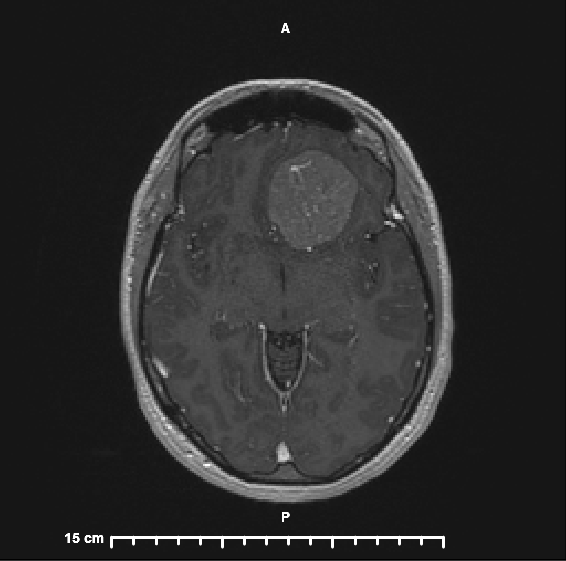

I have a brain tumor.

That is by far the strangest sentence I’ve ever spoken or typed. The doctors are 99% sure that it is a Benign Meningioma. I will be undergoing surgery to have it removed on December 13. I am still wrapping my head around this (no pun intended) but my overall feeling about it is that I knew there was something wrong; we figured out what it is and there is a plan to fix it!

I am thankful to have a doctor who listened to me and investigated what could be causing the symptoms I was experiencing. These tumors grow slowly, which makes them hard to diagnose because symptoms come on gradually. Mine has probably been growing for the last 5 years and it is a little bigger than a golf ball.

Honestly, I was a little embarrassed to bring this up to my doctor because it seemed so ridiculous but my Primary Care Doctor took it very seriously, ordering blood tests, and when those came back normal she ordered an MRI. That was to show if there was evidence of MS or any lesions; of those options MS seemed a lot more likely. If the MRI came back clean, she was going to refer me to Neurology to investigate more.

I had the MRI on a Wednesday morning (October 19) and truly wasn’t worried. Even when the technician told me he was looking over one of the images and would come in to pull me out in a couple of minutes. I still think about him and how awful it would be to find a tumor in a 36-year-old woman who you were just joking with before her test. Looking back, I had no idea of the battle I was about to get thrown in to and how much my life and my family’s lives were going to change.

Fast forward to that afternoon, we were getting ready to go to our nephew’s birthday party and I saw an email that I had a new test result in MyChart. In my mind, this meant everything was fine; if anything was seriously wrong, the result wouldn’t be released so fast, right? Boy, was I wrong! I opened up the report; the first line read “Left anterior cranial fossa extra-axial mass with imaging characteristics suspicious of meningioma. Associated mass effect as detailed.” What? What does that mean? By the way, you don’t get images on the MRI report. So, as I am reading all of the findings, I am googling the words, phrases, and entire sentences because I have no idea what any of them mean. I had 17 tabs open on my browser trying to piece it all together. I figured out that the MRI showed a brain tumor on my left frontal lobe. I know that with this information my entire world is about to change and I decided that I would wait to tell Sean until after the party and after we put Colin to bed.